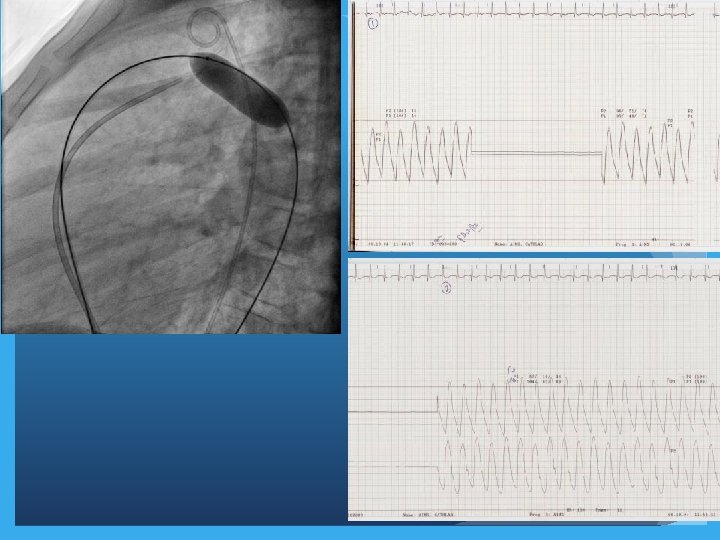

Special maneuvers in Cath lab �PDA occlusion to assess operability �Temporary occlusion of fenestrated Fontan to assess suitability of closure �Temporary occlusion of venous collaterals (pop off channels) post Glenn operation